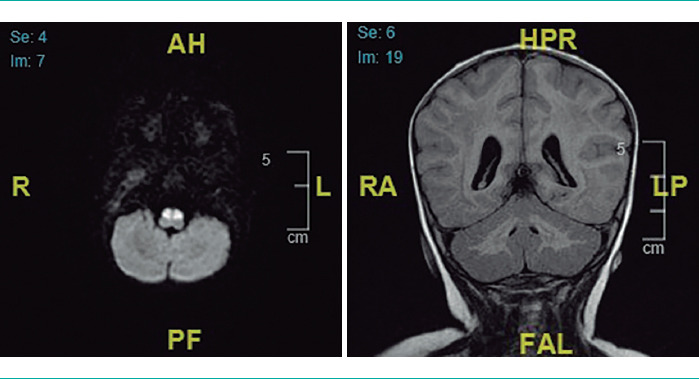

Case report: A 7-month-old male infant with no relevant history was admitted to a tertiary hospital as a result of vomiting, refusing food, and neurological symptoms. The episode was diagnosed as subacute rhombencephalitis based on the clinical findings and brain magnetic resonance imaging. Treatment with corticotherapy was undertaken, and led to gradual improvement. The patient was admitted once again three months later, due to an evident neurological regression after vaccination. A further MRI brain scan showed findings compatible with leukodystrophy, which was diagnosed as leukoencephalopathy with vanishing white matter after a genetic study. Treatment of symptoms was undertaken with follow-up by the home hospitalisation unit. However, the patient finally died at 15 months of age as a consequence of the evolution of his condition.